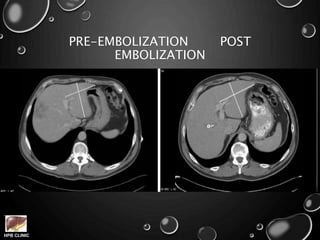

PRE-EMBOLIZATION POST

EMBOLIZATION

PORTAL VEIN EMBOLIZATION -

BASIS

Major liver resection

Inadequate future liver remnant volume

Liver failure

Increases post-op morbidity and mortality

WHAT IS PVE ?

Embolization of PV on the side to be resected

Concept – atrophy hypertrophy complex

Leads to hypertrophy of future liver remnant (FLR)

Allows major resection without post op liver failure